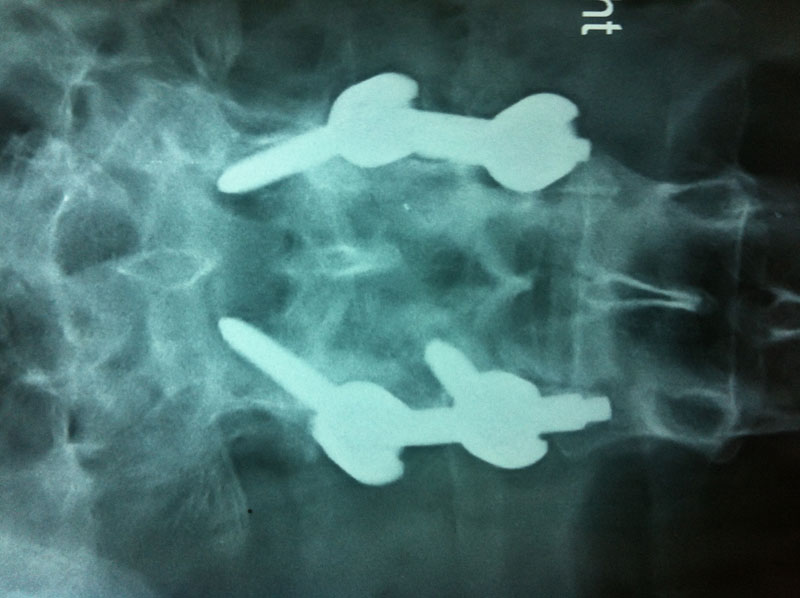

Surgery may be recommended if the conservative treatment options do not provide relief within two to three months. If leg or back pain limits normal activity, if there is weakness or numbness in the legs, if it is difficult to walk or stand, or if medication or physical therapy is ineffective, surgery may be necessary, most often spinal fusion.